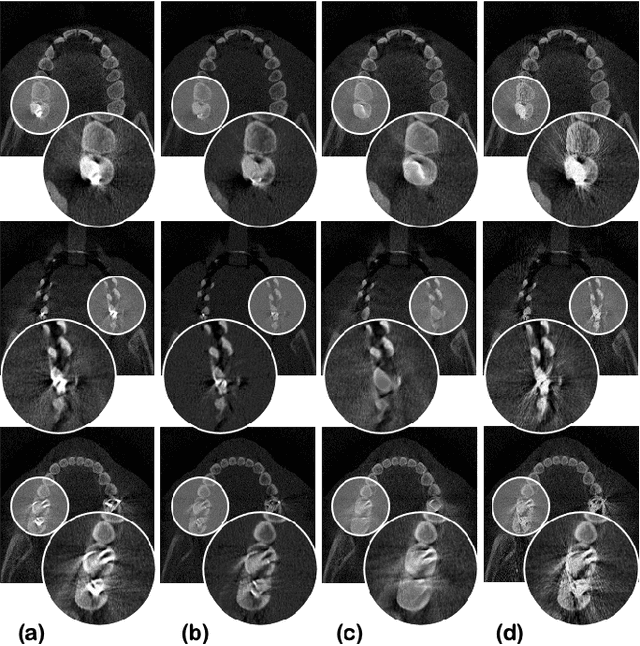

Metal artifact reduction (MAR) is one of the most important research topics in computed tomography (CT). With the advance of deep learning technology for image reconstruction,various deep learning methods have been also suggested for metal artifact removal, among which supervised learning methods are most popular. However, matched non-metal and metal image pairs are difficult to obtain in real CT acquisition. Recently, a promising unsupervised learning for MAR was proposed using feature disentanglement, but the resulting network architecture is complication and difficult to handle large size clinical images. To address this, here we propose a much simpler and much effective unsupervised MAR method for CT. The proposed method is based on a novel beta-cycleGAN architecture derived from the optimal transport theory for appropriate feature space disentanglement. Another important contribution is to show that attention mechanism is the key element to effectively remove the metal artifacts. Specifically, by adding the convolutional block attention module (CBAM) layers with a proper disentanglement parameter, experimental results confirm that we can get more improved MAR that preserves the detailed texture of the original image.